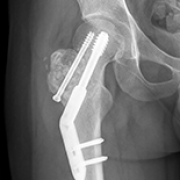

09 Nov 2024 : Clinical Research

Comparative Analysis of Extended Curettage with Plate Fixation and Extended Curettage with Intramedullary Nail Fixation for Campanacci Grade Ⅱ and International Society of Limb Salvage Zone H2 Giant Cell Tumors of the Proximal Femur: A Retrospective Study

Jiashi Song, Kaipeng Jin

DOI: 10.12659/MSM.945157

Med Sci Monit 2024; 30:e945157

Jiashi Song, Kaipeng Jin, Bing Liu

5,028